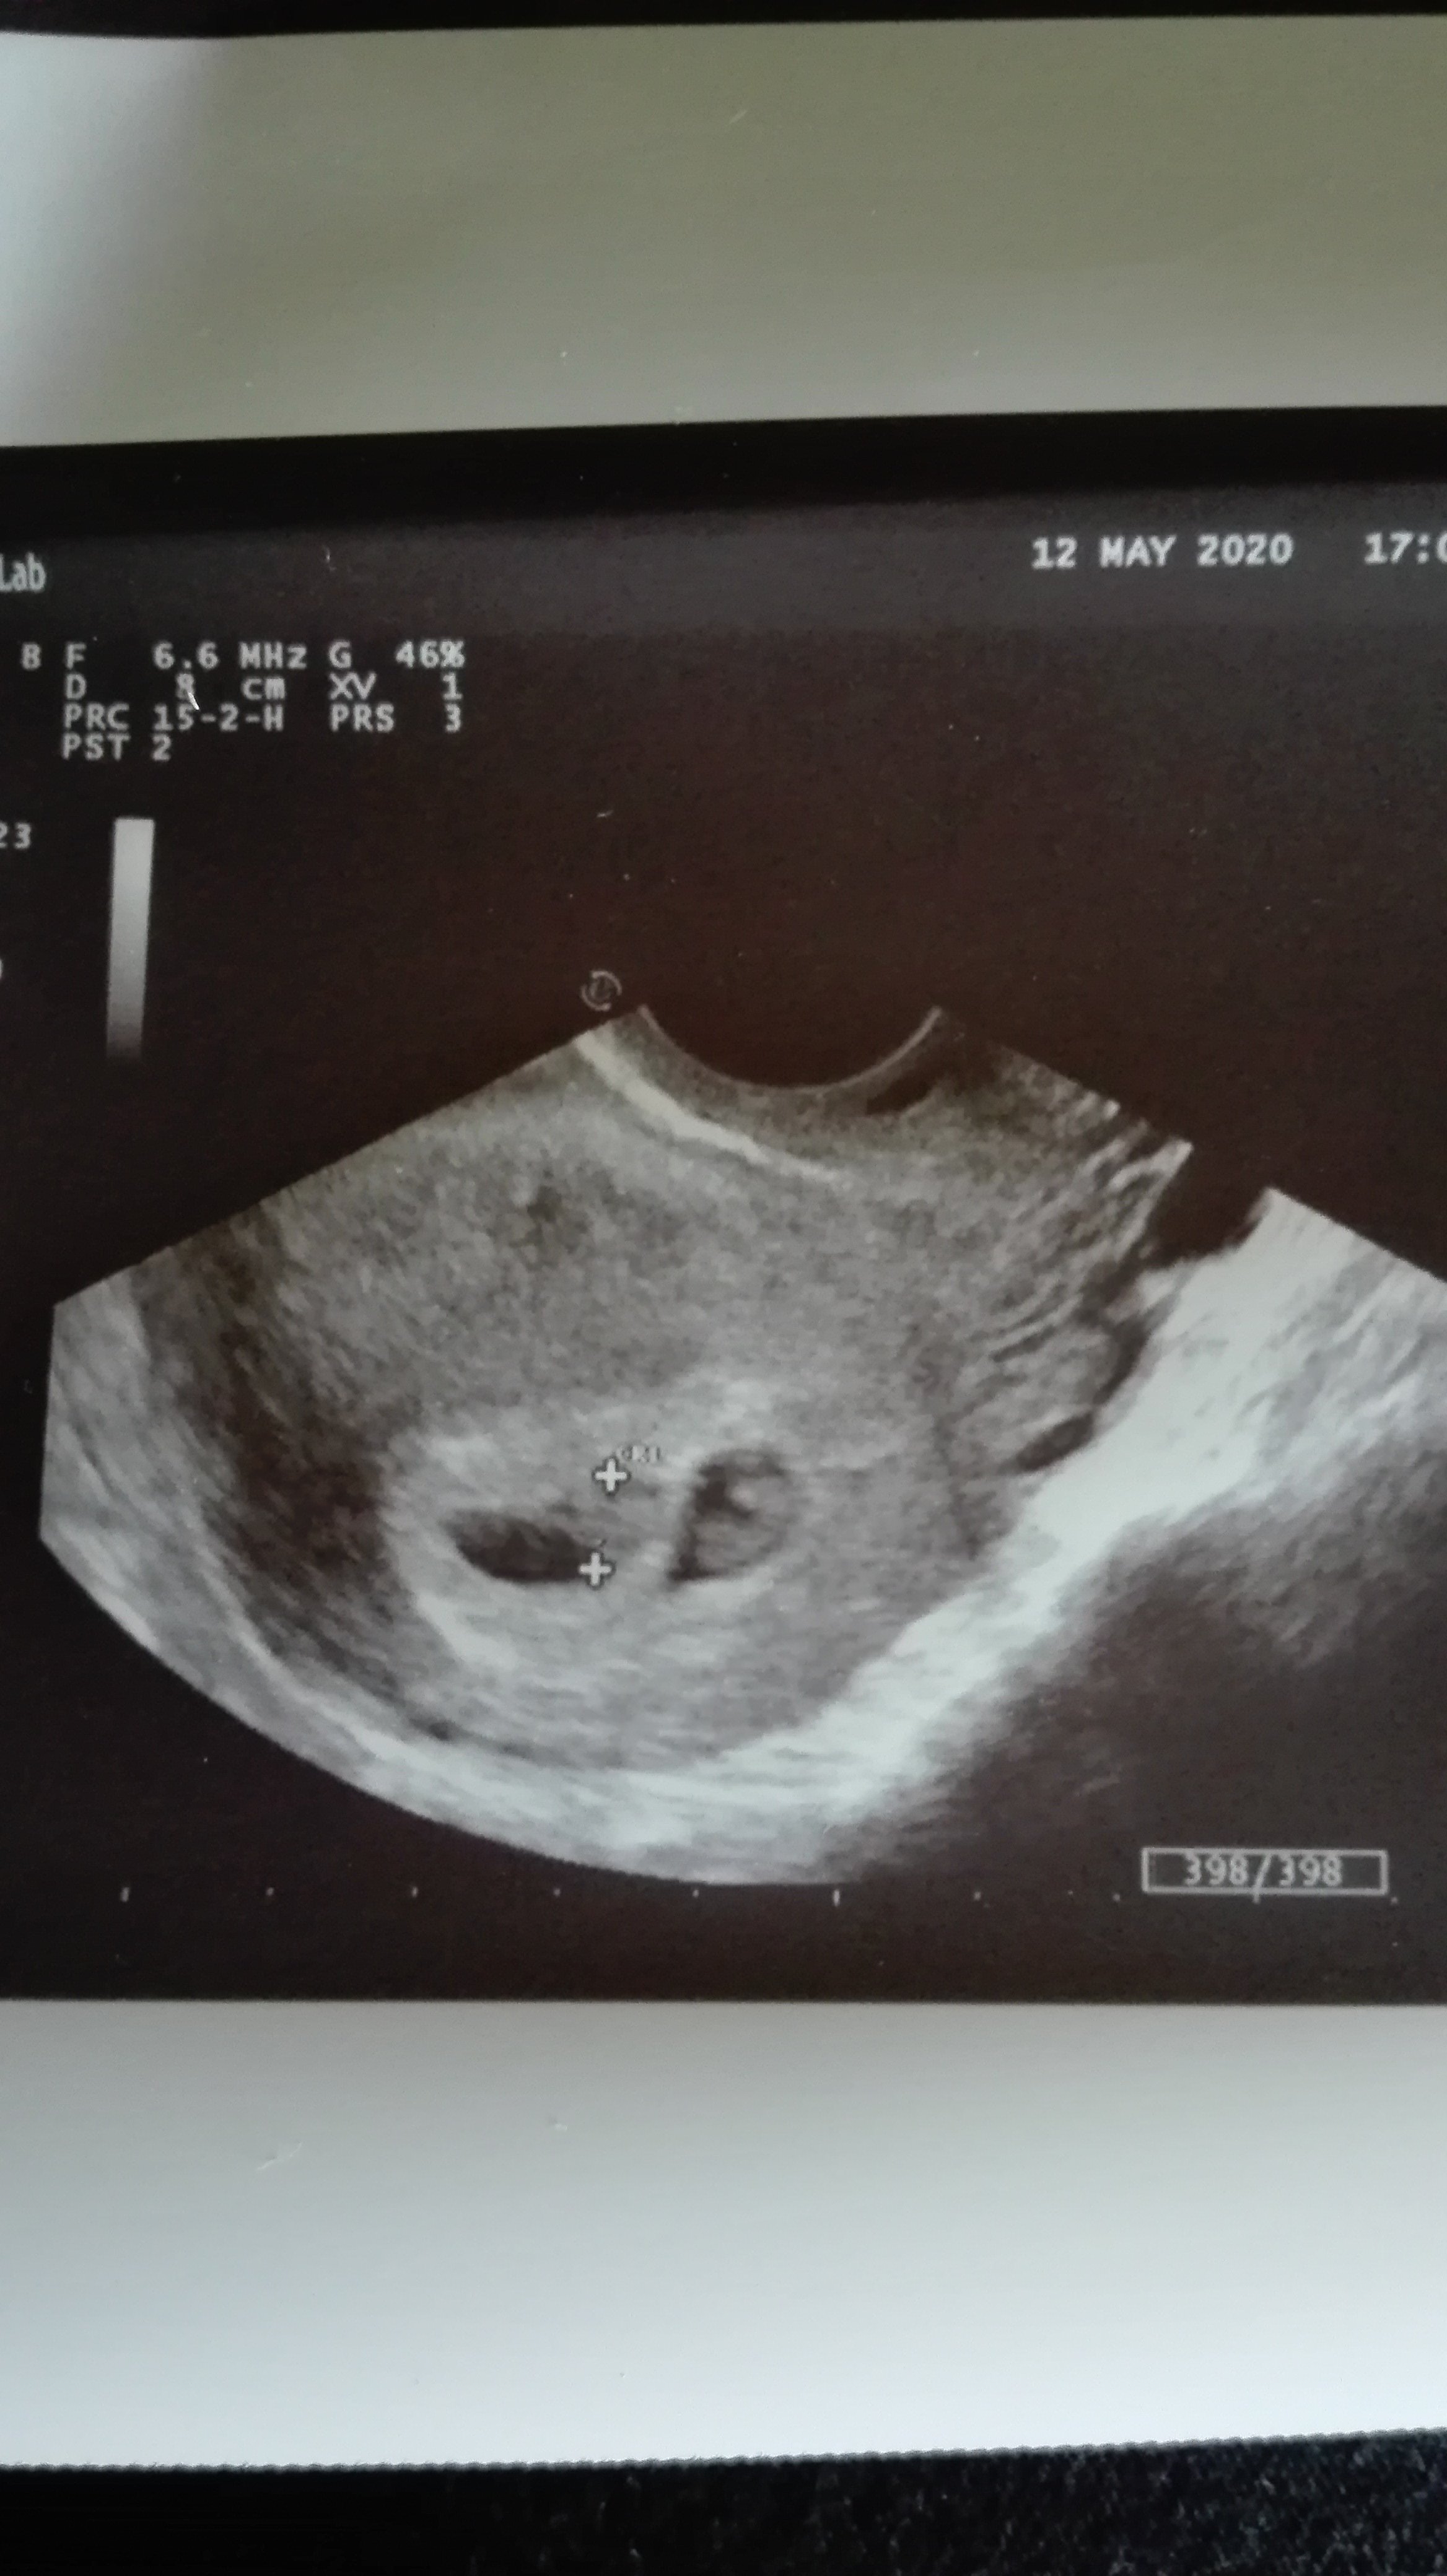

Gratuluję podwójnieAlez jestes skolowana... są dwa serduszka, dwoje dzieci. Boże

Jeju cudnie !!!! GratulujeAlez jestes skolowana... są dwa serduszka, dwoje dzieci. Boże

Zobacz załącznik 1118901

Wow ! Gratuluję! Ja zawsze chciałam bliźniaki i nigdy się nie udało (teraz jeszcze nie wiem)